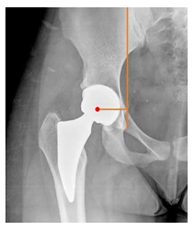

| Sharp angle | the angle between a line passing from the superior to the inferior acetabular rim and the horizontal plane | <42° | ![]() |